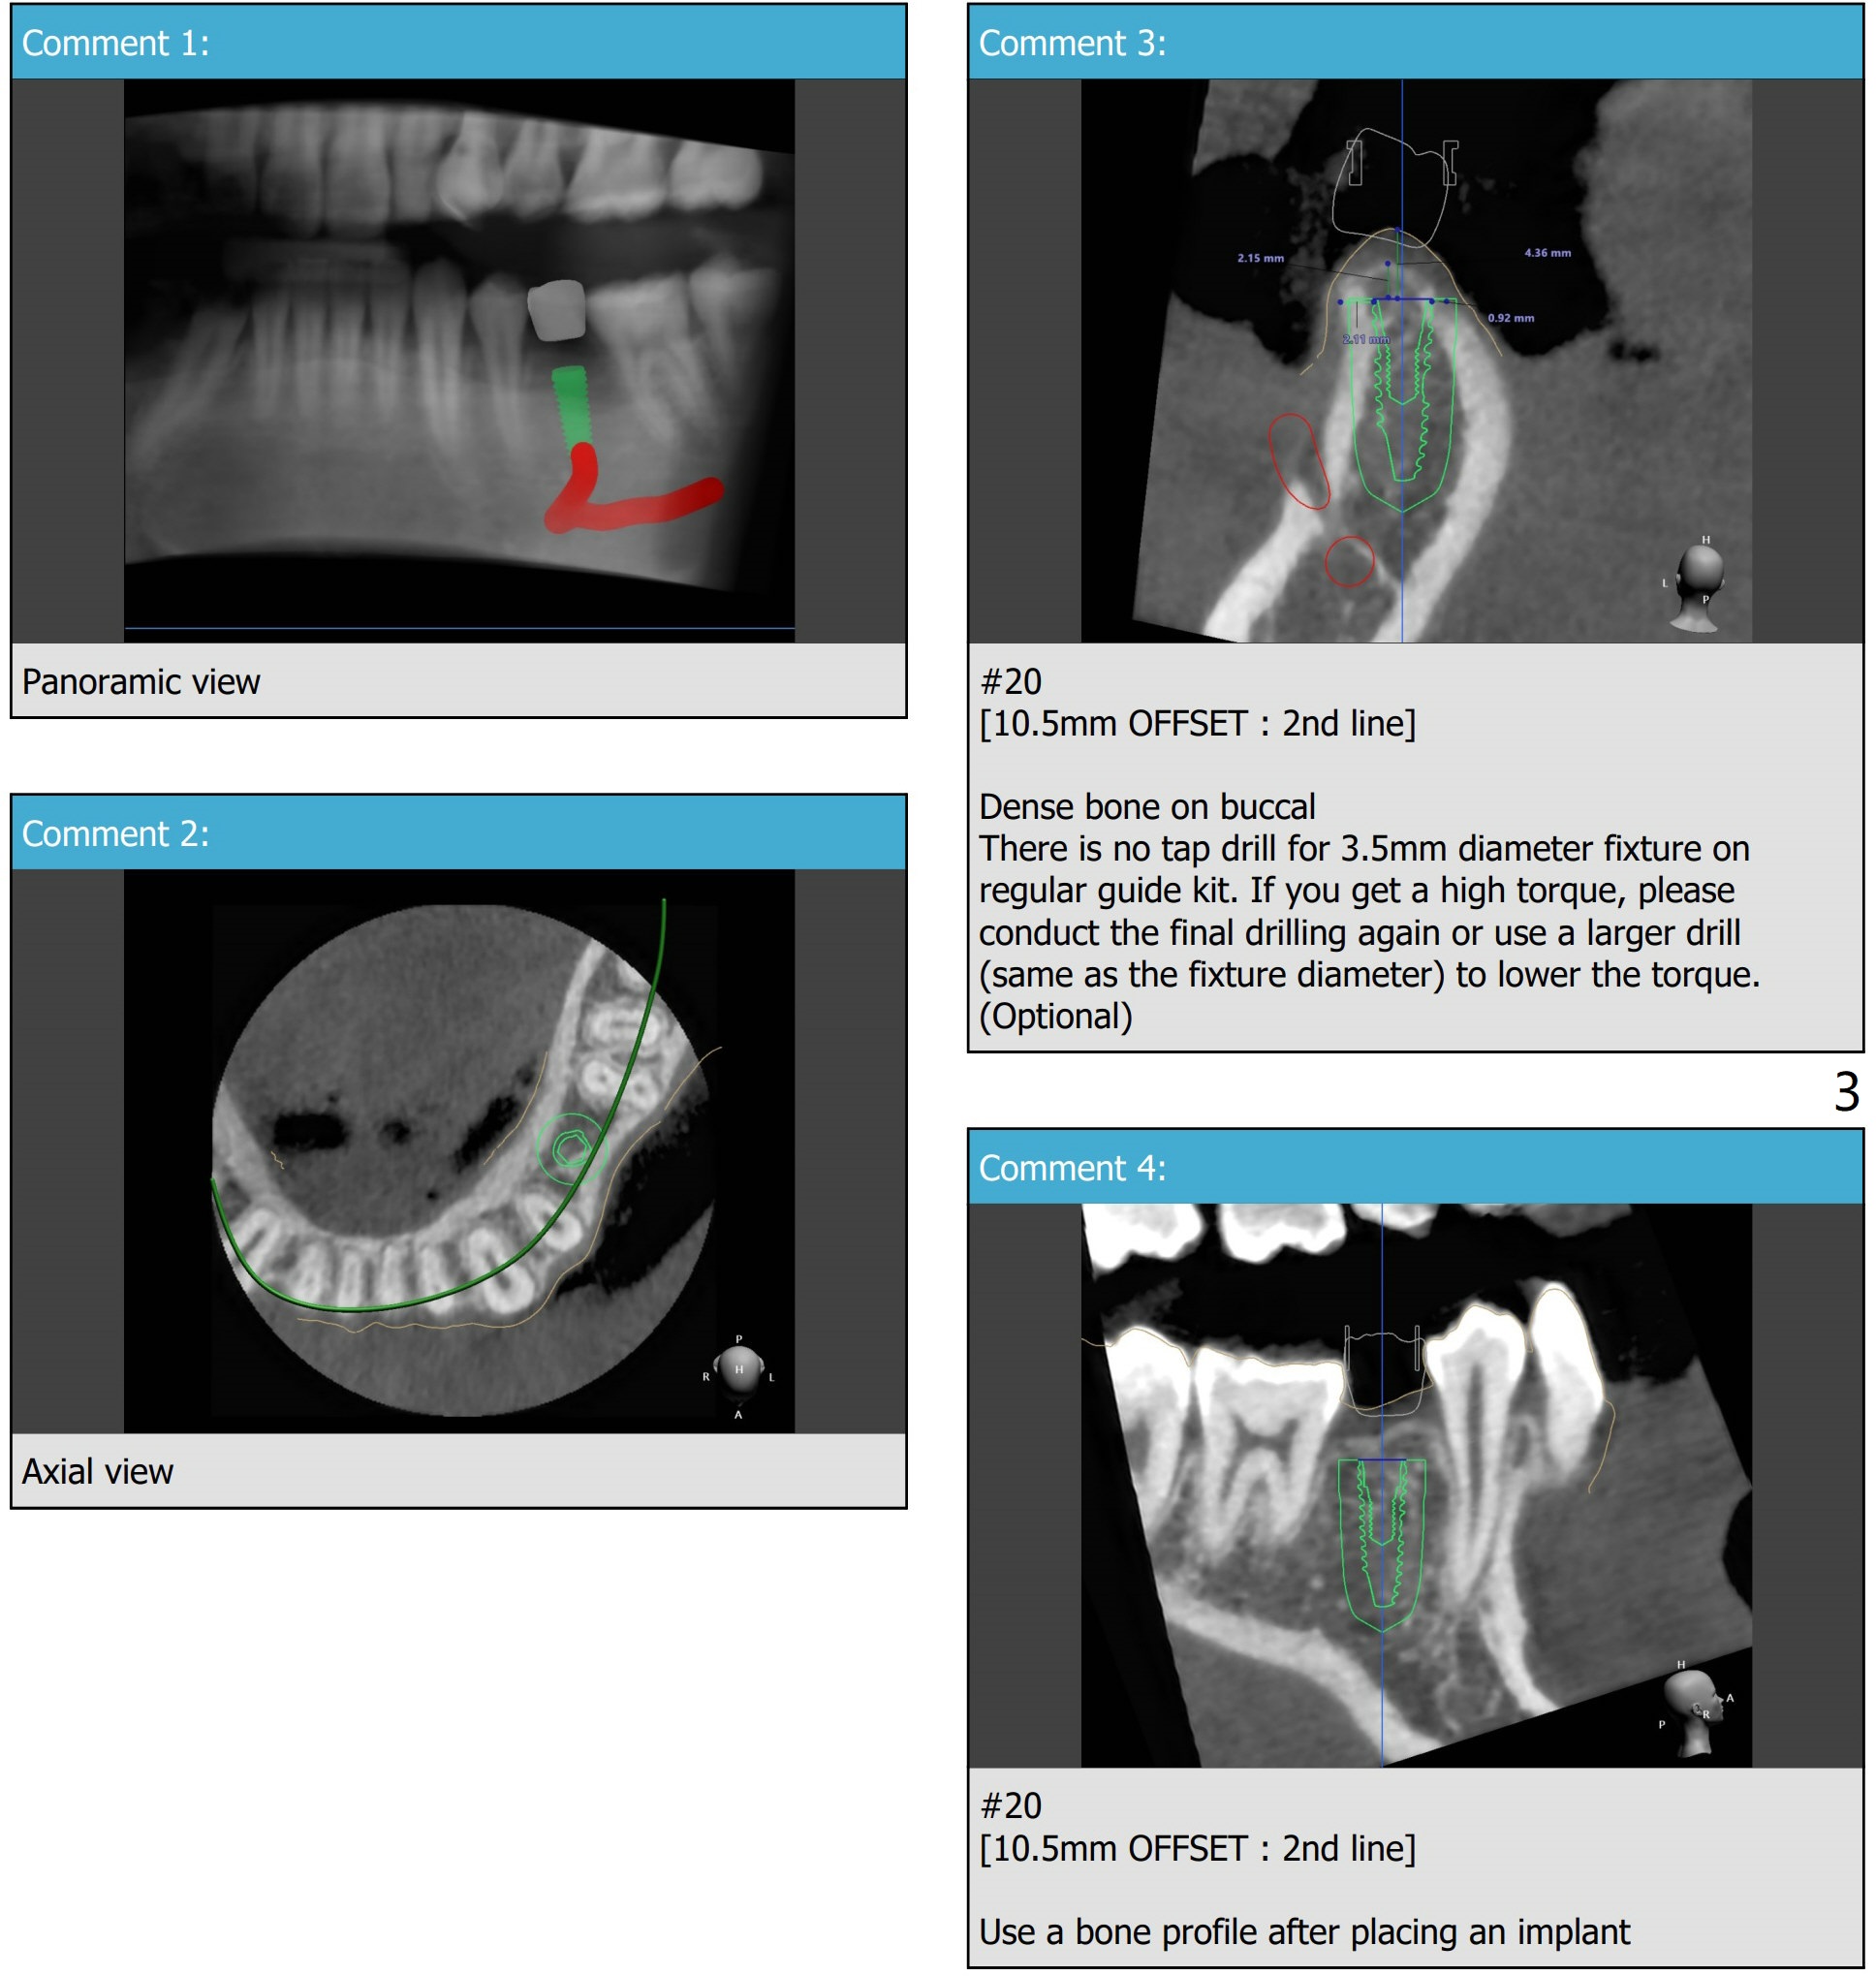

A 21-year-old man with congenital missing #20 has 1 pm appointment for oral scanning and CT for guide. Team viewer meeting is held at 5:30 pm.